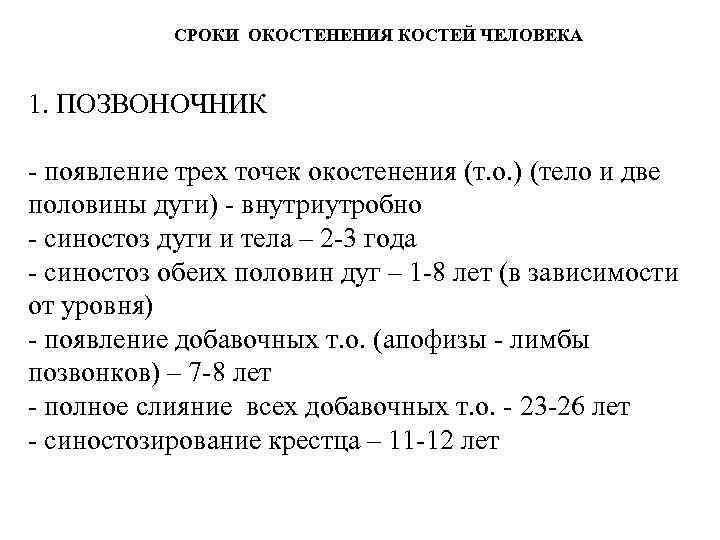

СРОКИ ОКОСТЕНЕНИЯ КОСТЕЙ ЧЕЛОВЕКА 1. ПОЗВОНОЧНИК - появление трех точек окостенения (т. о. ) (тело и две половины дуги) - внутриутробно - синостоз дуги и тела – 2 -3 года - синостоз обеих половин дуг – 1 -8 лет (в зависимости от уровня) - появление добавочных т. о. (апофизы - лимбы позвонков) – 7 -8 лет - полное слияние всех добавочных т. о. - 23 -26 лет - синостозирование крестца – 11 -12 лет

СРОКИ ОКОСТЕНЕНИЯ КОСТЕЙ ЧЕЛОВЕКА 1. ПОЗВОНОЧНИК - появление трех точек окостенения (т. о. ) (тело и две половины дуги) - внутриутробно - синостоз дуги и тела – 2 -3 года - синостоз обеих половин дуг – 1 -8 лет (в зависимости от уровня) - появление добавочных т. о. (апофизы - лимбы позвонков) – 7 -8 лет - полное слияние всех добавочных т. о. - 23 -26 лет - синостозирование крестца – 11 -12 лет